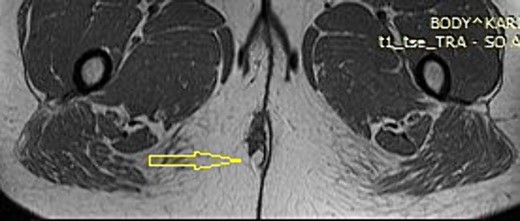

A 37-year-old female patient presented to the outpatient department with a palpable mass in the perianal region on the right side. The patient had two normal pregnancies with spontaneous deliveries 13 and 9 years ago, respectively. The medical history was remarkable for an operative treatment of perianal abscess 6 months before the examination. At the time of the surgery, the patient presented with pain and fluctuating swelling in the perianal region. An incision was performed with the evacuation of a small collection of dark fluid. After the procedure, a continuous experience with occasional pain and uncomfortable feeling in the perianal region was present. Magnetic resonance imaging (MRI) revealed a 4.5 × 2.5 cm perianal mass slightly towards the right side. It showed mixed intermediate and high signal intensity, attributed to the recurrent puss component. There was an associated diffusion restriction but no avid enhancement after intravenous contrast administration. The opacity of surrounding adipose tissue was noted. The nature of the mass was interpreted as recurrent abscess formation (Fig. 1).

A 33-year-old female patient presented to the emergency department with pain and swelling in the perianal region. The patient was previously treated (a few months ago) for a perianal abscess. MRI revealed a 3.5 × 2 cm mass in the right perianal region pressing on and indenting the right aspect of the distal external sphincter. This mass showed mixed intermediate and high signal intensity. There was an associated diffusion restriction but no avid enhancement after intravenous contrast administration. No fatty components were observed. The exact nature of this mass was indeterminate. (Fig. 3). The patient had two spontaneous parturitions 6 and 3 years precedent, with a placenta defect noted on the second delivery that required manual revision of the uterine cavity.